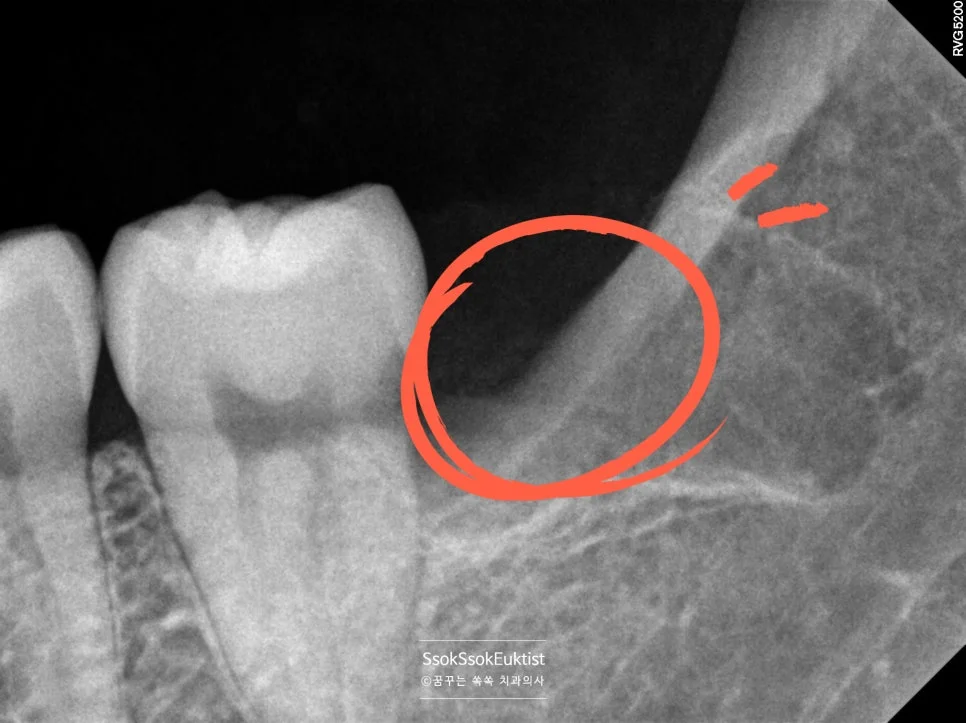

왼쪽 아래 매복 사랑니 발치 후 방사선

왼쪽 아래 매복 사랑니 발치 후 X-ray

오른쪽 아래 매복 사랑니 발치 후 방사선

오른쪽 아래 매복 사랑니 발치 후 X-ray